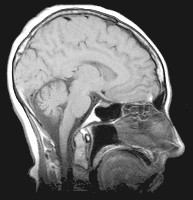

A magnetic resonance imaging machine takes pictures of your body in 'slices' ... it scans it one slice at a time, and then a computer is used to make a full three-dimensional image of the part of your body being examined. At the right, you can see an MRI picture of one 'slice' through a person's head. Much more detail is possible than with an x-ray, and as many 'slices' can be photographed as necessary, without harming the patient.